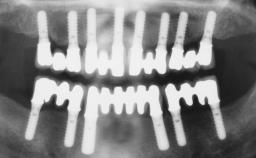

Conventional Loading of Six Implants in the Mandible and Final Restoration with a Full-Arch Metal-Ceramic FDP

# of Implants 6

Type of Implants One-Piece